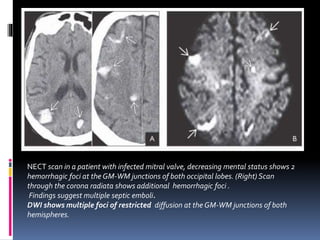

NECT scan in a patient with infected mitral valve, decreasing mental status shows 2

hemorrhagic foci at the GM-WM junctions of both occipital lobes. (Right) Scan

through the corona radiata shows additional hemorrhagic foci .

Findings suggest multiple septic emboli.

DWI shows multiple foci of restricted diffusion at the GM-WM junctions of both

hemispheres.